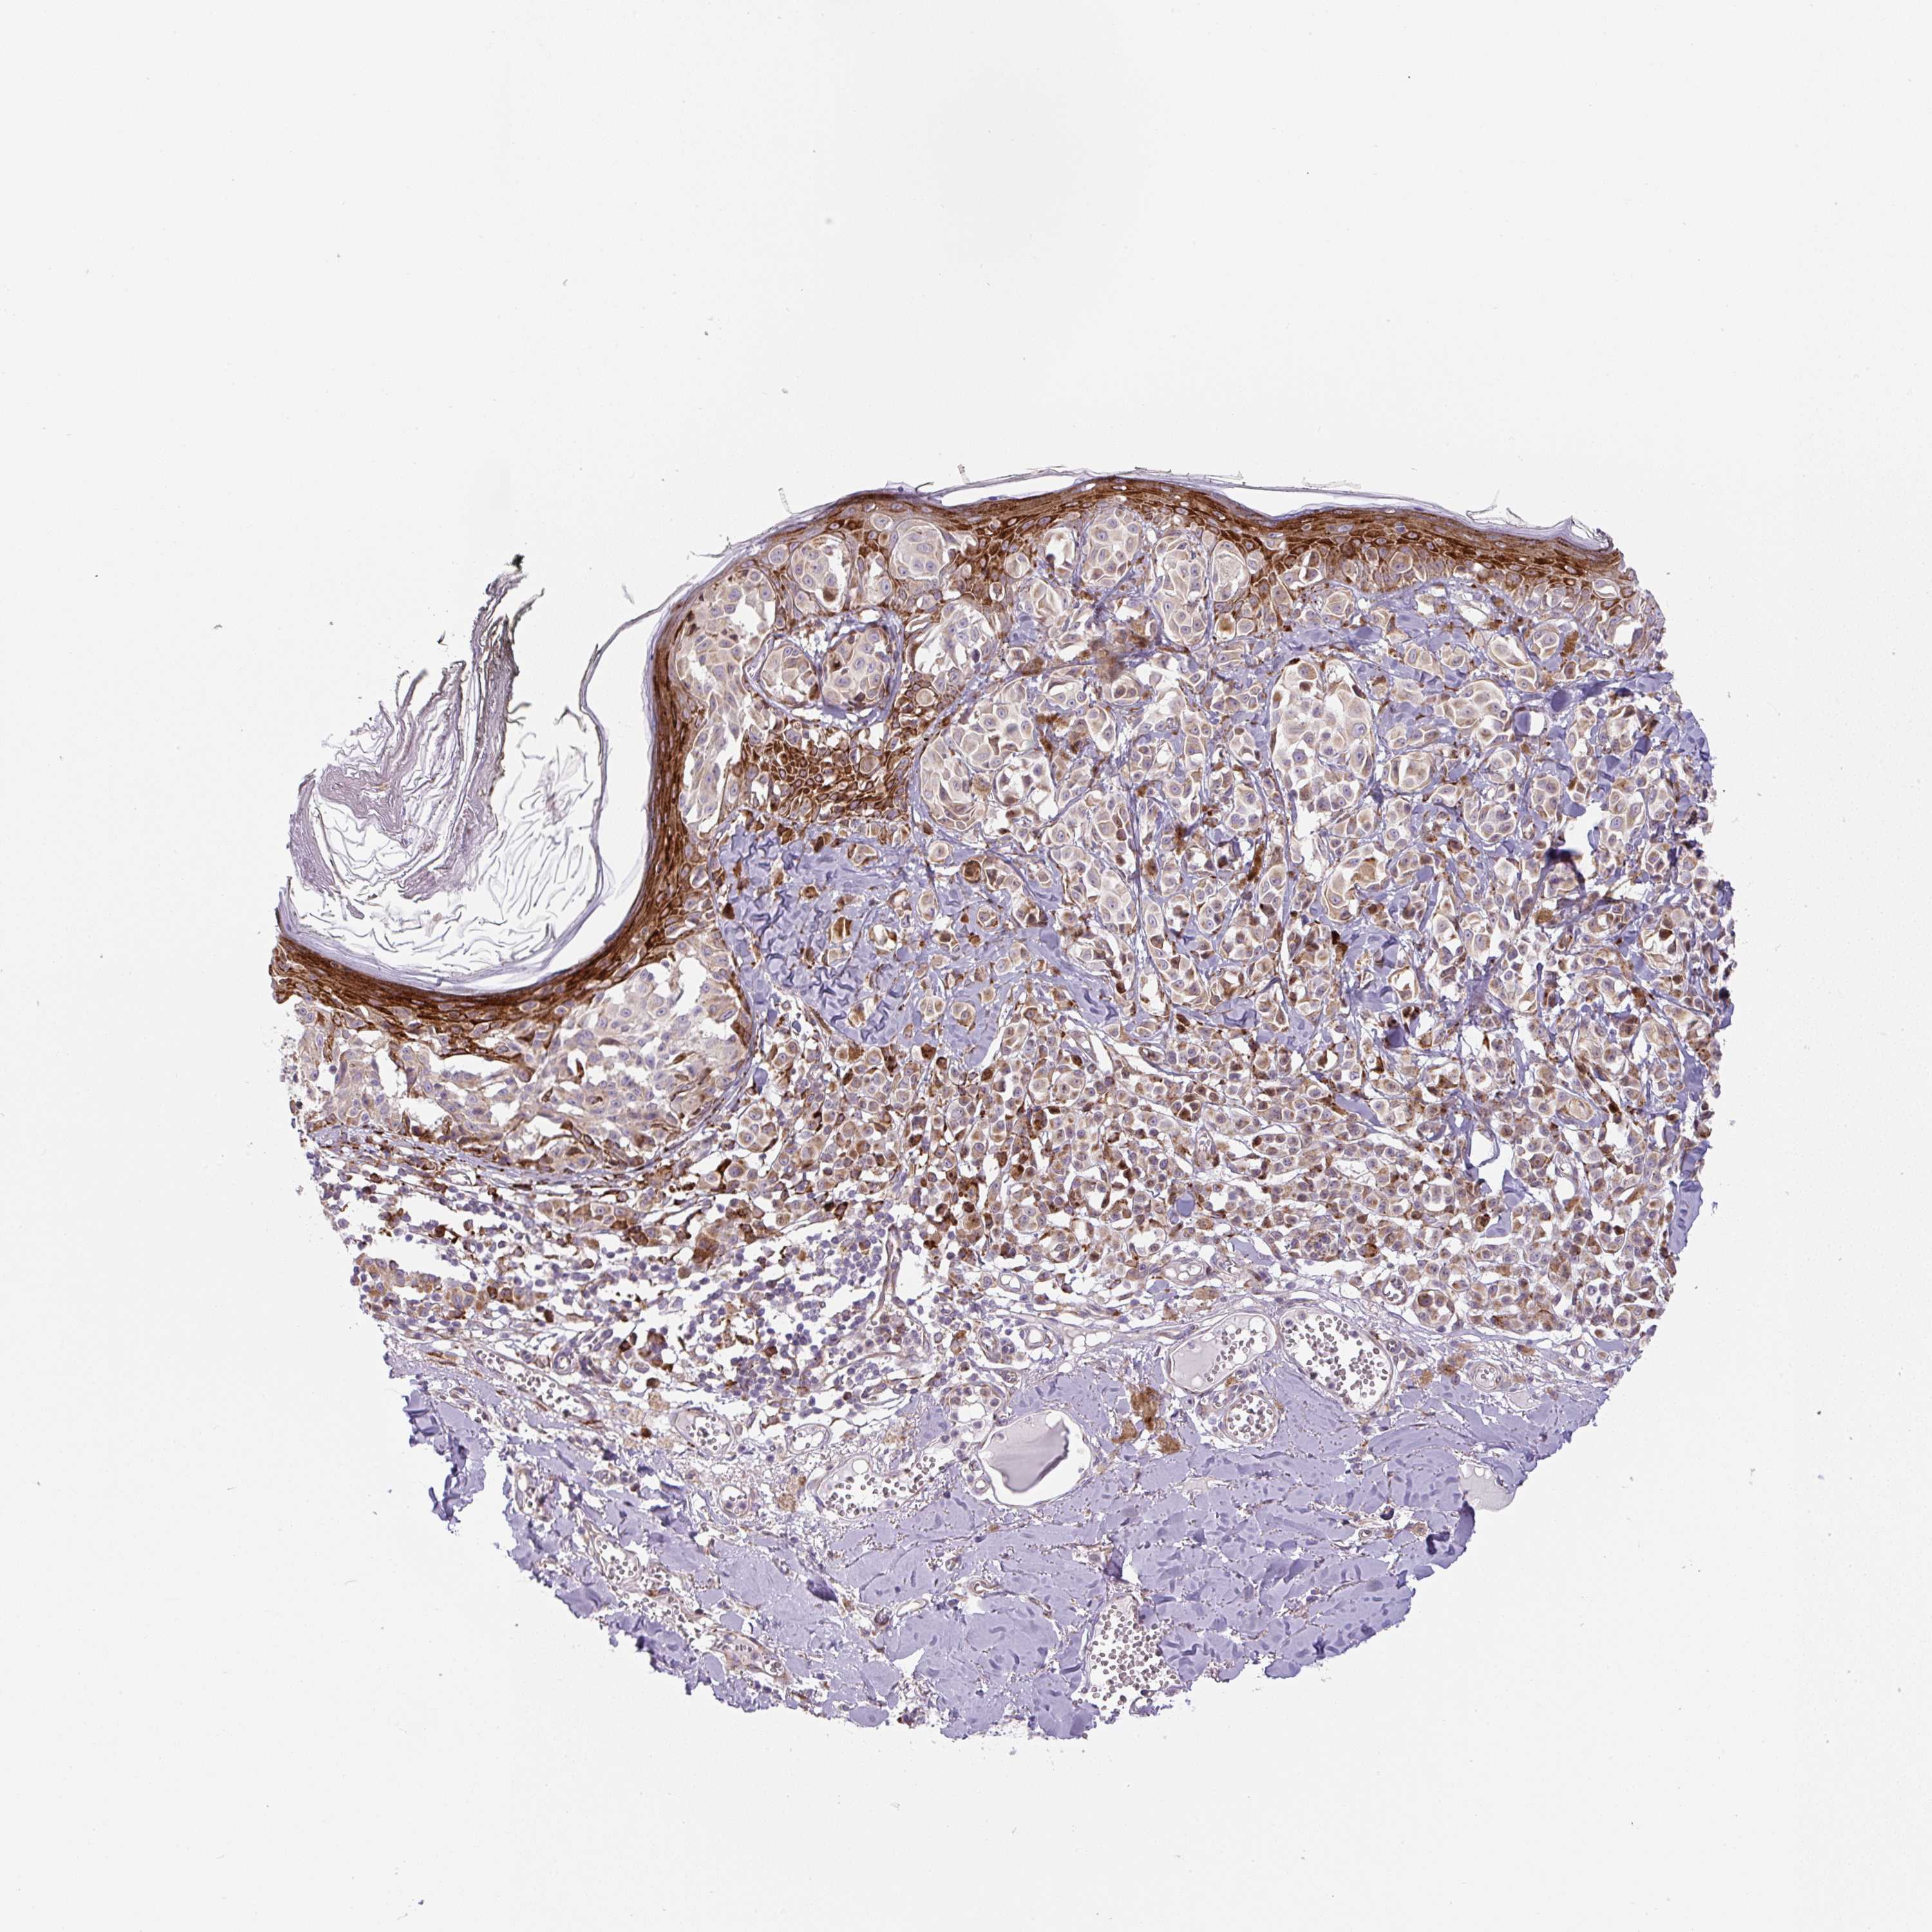

MELANOMA - Protein expressioni

A mouse-over function shows sample information and annotation data. Click on an image to view it in a full screen mode. Samples can be filtered based on level of antibody staining by selecting one or several of the following categories: high, medium, low and not detected. The assay and annotation is described here.

Note that samples used for immunohistochemistry by the Human Protein Atlas do not correspond to samples in the TCGA dataset.

Antibody stainingi

Antibody staining in the annotated cell types in the current human tissue is reported as not detected, low, medium, or high, based on conventional immunohistochemistry profiling in selected tissues. This score is based on the combination of the staining intensity and fraction of stained cells.

Each image is clickable and will lead to virtual microscopy that enables deeper exploration of all samples and also displays staining intensity scores, fraction scores and subcellular localization as well as patient and tissue information for each sample.

Antibody HPA054579

Staining

High

Medium

Low

Not detected

Intensity

Strong

Moderate

Weak

Negative

Quantity

>75%

75%-25%

<25%

None

Location

Nuclear

Cytoplasmic/membranous

Cytoplasmic/membranous,nuclear

Malignant melanoma, NOS

Malignant melanoma, Metastatic site